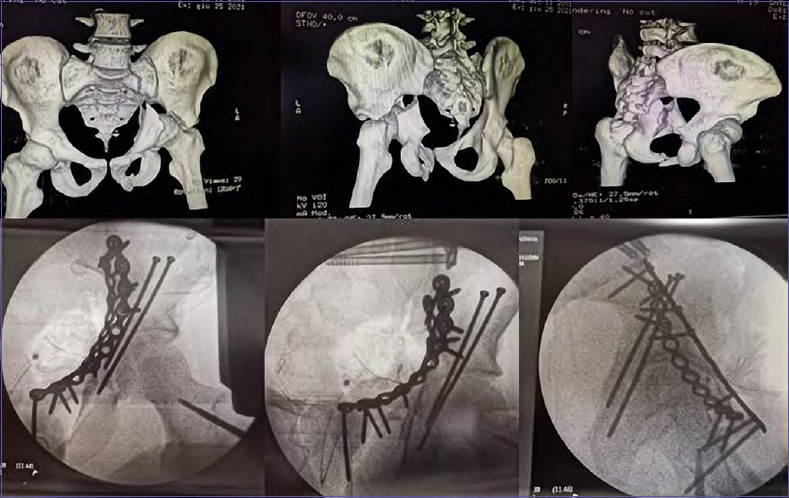

Accurate classification of acetabular fractures is therefore possible on the basis of x-rays, which represent the first step in the decision-making process. The second step is 2D CT, which can detect many important details that cannot be seen with x-ray alone. The imaging process ends with 3D CT, which allows to obtain a more accurate characterization of the fracture to classify it in the best possible way; this facilitates the choice of surgical routes and anticipates the maneuvers to be performed to obtain good reduction 13.

The aim of surgical treatment is to obtain accurate reduction and restoration of joint congruence (Figs. 6,7.1,7.2).

Figure 6.19 years old young man: complex pelvic fracture treated with screw and plates.

Figure 7A-B.81 years old man: complex pelvic fracture treated with plates.